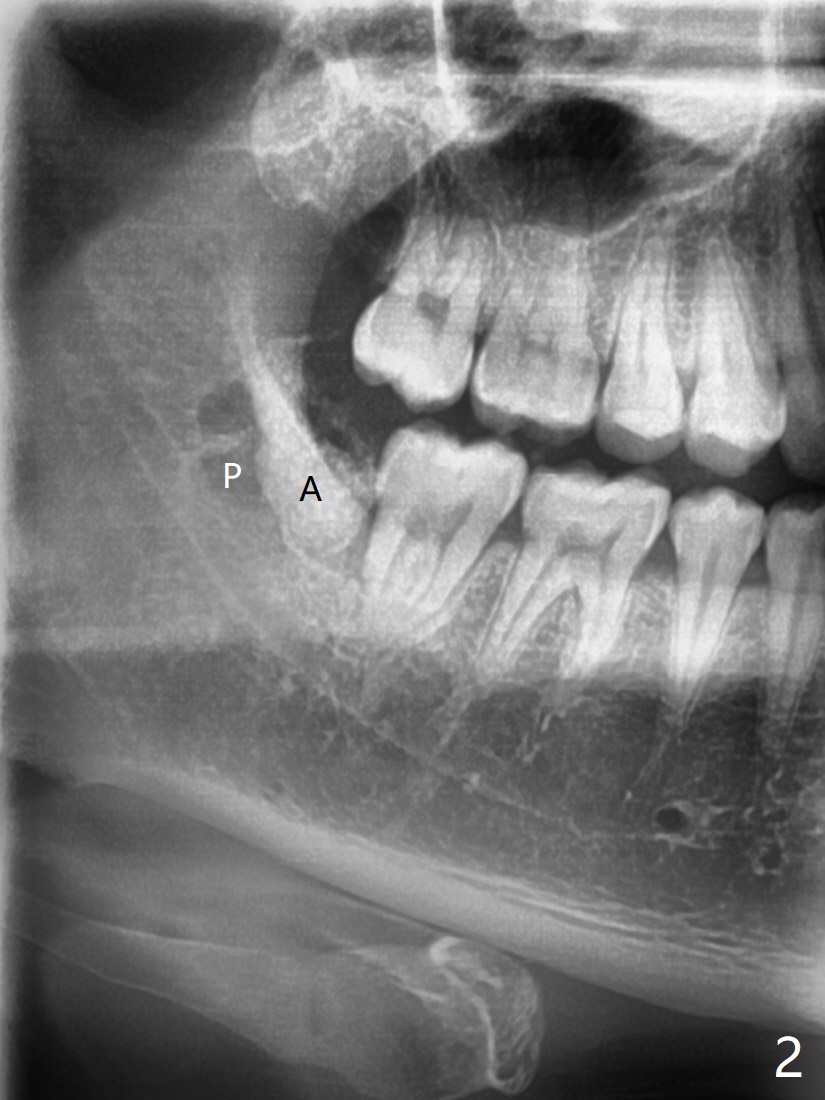

Dental Sac vs. Bone Loss

A 23-year-old man with poor oral hygiene presents to clinic with pain at #1 and 32. Because of bone loss between #31 and 32 (Fig.1 *), Bond Apatite (1 cc, Fig.2 A) is placed in the defect area following insertion of Collagen Plug in the sockets (P, a half). The other half of the Plug is placed coronal to Bond Apatite before suturing with 4-0 PGA.